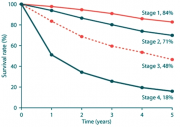

| 07:15, 7 בספטמבר 2012 | Breastgraph412.png (קובץ) |  |

63 קילו־בייטים | Motyk | 1 | |